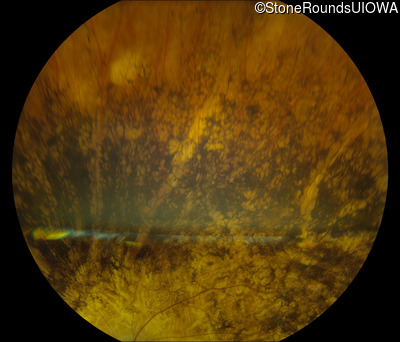

Fundus Photography - Left - Light Perception

Exemplar

Fundus Montage - Left - Light Perception